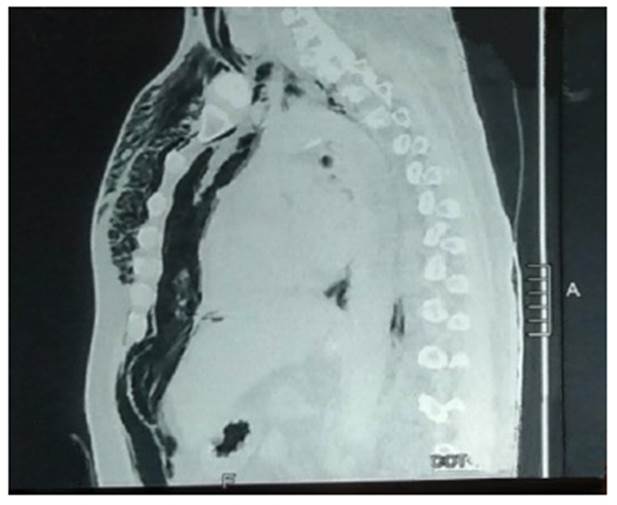

El paciente ingresó a la Unidad de Cuidados Intensivos con los siguientes diagnósticos: insuficiencia respiratoria, sepsis por infección por COVID-19 y diabetes mellitus 2 compensada. Se planteó la siguiente terapéutica: nada por vía oral, ClNa 90/000 + ClK 20 % (EV a 80 cc/h), ceftriaxona 2 g (EV c/24 h), azitromicina 500 mg (SNG c/24 h), ivermectina 80 gotas (SNG c/24 h), vitamina C 2,5 g (EV c/12 h), zinc 30 mg (SNG c/12 h), paracetamol 1 g (EV condicional a T > 38,5 °C), hemoglucotest (c/8 h), soporte de oxígeno, control de funciones vitales, balance hidroelectrolítico y con estrategia respiratoria de pronación. Al inicio del segundo día de hospitalización, presenta hemodinamia estable, la cual se deteriora de manera espontánea y progresiva; al promediar el medio día, presenta disminución de la saturación de 95 % a 60 %, FR: 46 veces por minuto, FC: 105 por minuto, PA: 150/97 mmHg, encefalopatía, agitación psicomotriz, cianosis central y periférica, signos de hipoperfusión, y con caída brusca del PO₂; además, presenta enfisema subcutáneo en la región cervical. Debido a la inestabilidad, se protege la vía aérea con intubación endotraqueal. La tomografía helicoidal multicorte de tórax muestra una imagen de neumomediastino espontáneo (Figura 2) que se extiende a las zonas cervical y abdominal (Figura 3), y se evidencia el efecto Macklin espontáneo.

Figura 3 Tomografía helicoidal de tórax (vista sagital). Se observa aire libre que diseca áreas anatómicas y se desplaza hacia diversas regiones topográficas